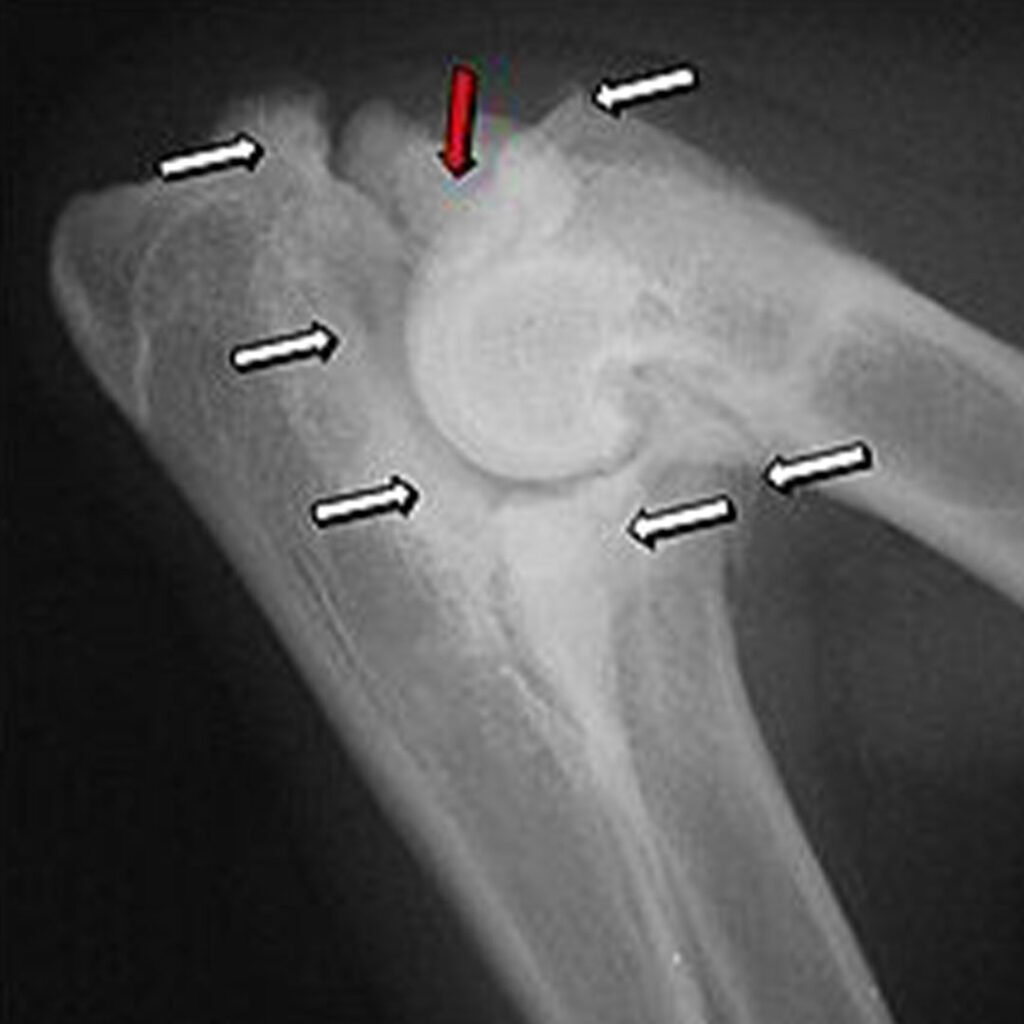

Fragmentierter Processus Coronoideus medialis (FCP):

Hierbei löst sich ein kleines Knochenstück der Elle (Ulna) ab. Dieses abgelöste Fragment kann im Gelenk Schmerzen und Entzündungen verursachen.

Ununited Anconeal Process (UAP):

Ein Teil der Elle (der sogenannte Anconeus) verbindet sich nicht korrekt mit dem restlichen Knochen, was Instabilität und Schmerzen verursacht.

Inkongruenz des Ellenbogengelenks:

Die drei Knochen des Ellenbogengelenks passen nicht richtig zueinander, was zu einer ungleichmäßigen Belastung und zu Schäden im Gelenk führt.

ED – Grad 0: Normal – keine Osteophyten oder Sklerose

ED – Grad I: Milde Arthrose – Osteophyten kleiner als 2 mm oder Sklerose der Gelenkfläche der Elle

ED – Grad II: Moderate Arthrose – Osteophyten zwischen 2 und 5 mm groß

ED – Grad III: Schwere Arthrose – Osteophyten größer als 5 mm